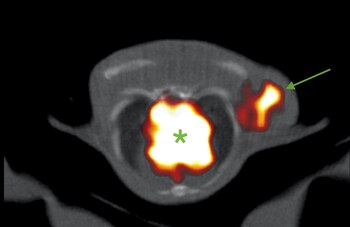

En la inmuno-PET los anticuerpos guían el radiofármaco hasta los procesos o tejidos que es necesario estudiar, lo que permite observar en tiempo real y en organismos vivos los cambios moleculares relacionados con el inicio de enfermedades -o etapas muy tempranas-, su progresión y su respuesta a los medicamentos.

Una de las áreas de aplicación más prometedoras es la oncología, donde se ha demostrado su potencial para la detección, seguimiento y comprobación de respuesta al tratamiento en tumores de pulmón, hematológicos y de mama.

La doctora Mulero, en colaboración con Jorge L. Martínez Torrecuadrada, jefe de la Unidad de Producción de Proteínas del CNIO, entre otros expertos, ha observado con inmuno-PET las metástasis del tipo más agresivo de cáncer de mama, el triple negativo. En este caso emplearon nanobodies, anticuerpos de los camélidos (camellos, llamas y alpacas) y los tiburones, con un tamaño diez veces menor que los anticuerpos humanos, y comprobaron que llegan a su objetivo con más facilidad. Además, su menor tamaño permite al cuerpo eliminar más rápidamente el radiofármaco.